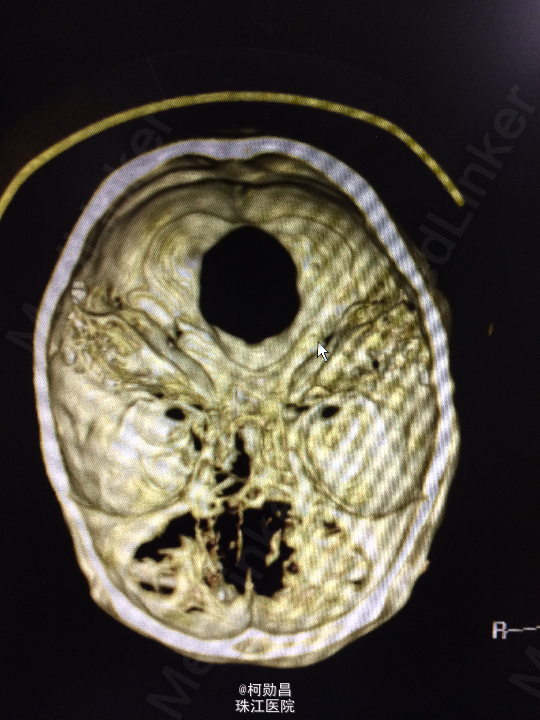

主诉:头痛伴左眼视力下降半年 病史:患者46岁男性,缘于半年前无明显诱因出现头痛,当时未予特殊处理,后症状进行性加重,并发左眼视力下降,于当地医院行头颅CT及MR检查提示颅内占位,为进一步治疗而入我院。 既往病史:5年前曾患鼻咽癌

查体:神志清楚,对答流利,左侧眼裂变小,左侧瞳孔散大,直径4mm,对光反射迟钝,左眼视力下降。右侧正常。 辅助检查:头颅MR提示前颅底筛沟通病变

诊断:鼻咽癌脑转移 处理:全麻下行颅筛沟通占位切除术,术后病理提示:鼻咽非角化鼻咽癌脑转移